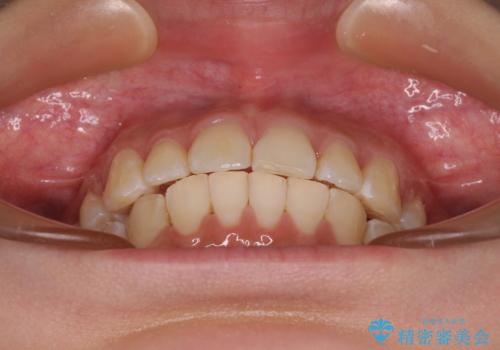

- 口を閉じたときに唇の間から飛び出してくる前歯を気にして来院された患者様です。

骨格的に上顎骨が前方位にあるため、左右の第一小臼歯を抜歯し、ワイヤー装置にて咬み合わせを整えていくこととしました。

前歯の突出感が改善されるだけでなく、奥歯の咬み合わせも改善され、食いしばりをしにくい状態に仕上げることができました。